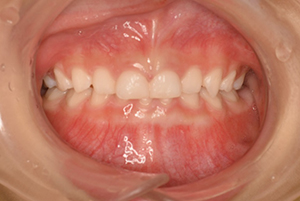

前歯が噛み合っていない状態

レントゲン写真 治療内容・期間 6歳から虫歯の治療で通っていただいていた患者さんです。 9歳のときのお口の中が左の写真です。 下の前歯はすでにガタガタになっています。また、写真ではわかりにくいですが、受け口ぎみです。開口もあり、前歯が噛み合っていない状態です。 顎顔面矯正を5年間、装置をつけたり外したりしながら継続し...